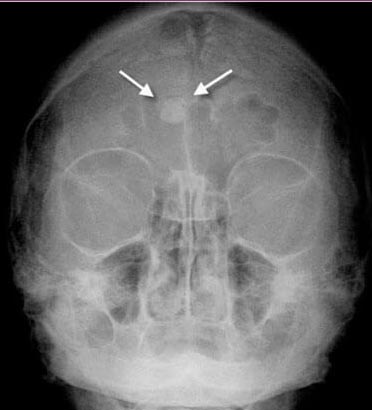

Фото фронтита на рентгеновском снимке

Для диагностики используют данные анамнеза, жалобы больного, результаты рентгенологических исследований придаточных пазух носа, а также данные КТ или МРТ. Лечение хронического фронтита у взрослых зависит от его формы, выраженности симптомов и наличия осложнений.

- рентгенография придаточных пазух, дает возможность определить отечность и скопление содержимого пазух, однако распознать природу воспалительного экссудата данный метод не способен;

Окончательный диагноз не ставиться по данным эндоскопии, определяющими являются рентгенография и КТ.